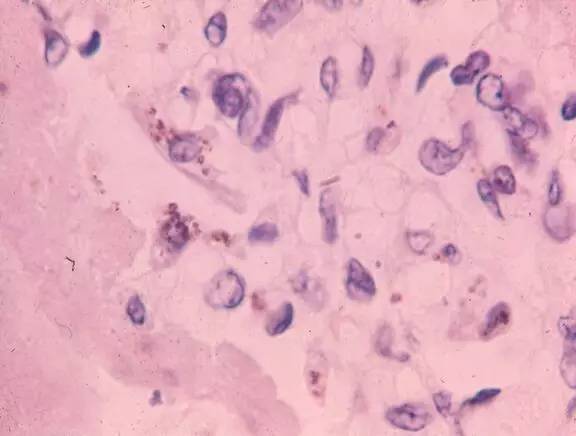

慢性宫内缺氧引起后腺泡肺毛细血管增生或产生新生血管

缺氧,高碳酸血症或酸中毒导致功能性肺毛细血管收缩

炎症导致功能性肺毛细血管收缩